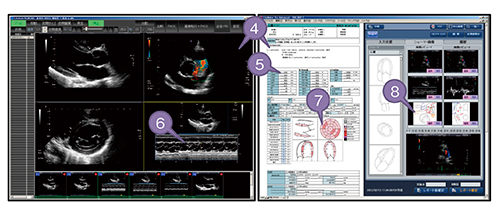

超音波検査では,短時間に検査して迅速にレポートを作成する必要がある。一方,緊急時に名前が確認できないまま検査したり,患者名を切り替えずに検査するミスもある。このような状況を想定してスムーズに運用できるシステムを開発した(図8)。具体的には,(1) オーダを取り込む,(2) 診察券などで患者を同定して検査装置にオーダ情報を送信する,(3) レポート端末で患者情報修正,画像選択などの検像をする,という流れにした。さらに,レポート作成(図9)は,(4) 画像とレポートの一体化,(5) 装置の計測値取り込み,(6) 計測漏れのレポート端末での再計測,(7) Wall Motion Scoring,(8) シェーマの選択および描画などにより,短時間でわかりやすいレポートが仕上がるようにした。

図8 超音波レポートシステムのワークフロー(数字は本文の説明番号)

図9 超音波システムのレポート作成画面(数字は本文の説明番号)